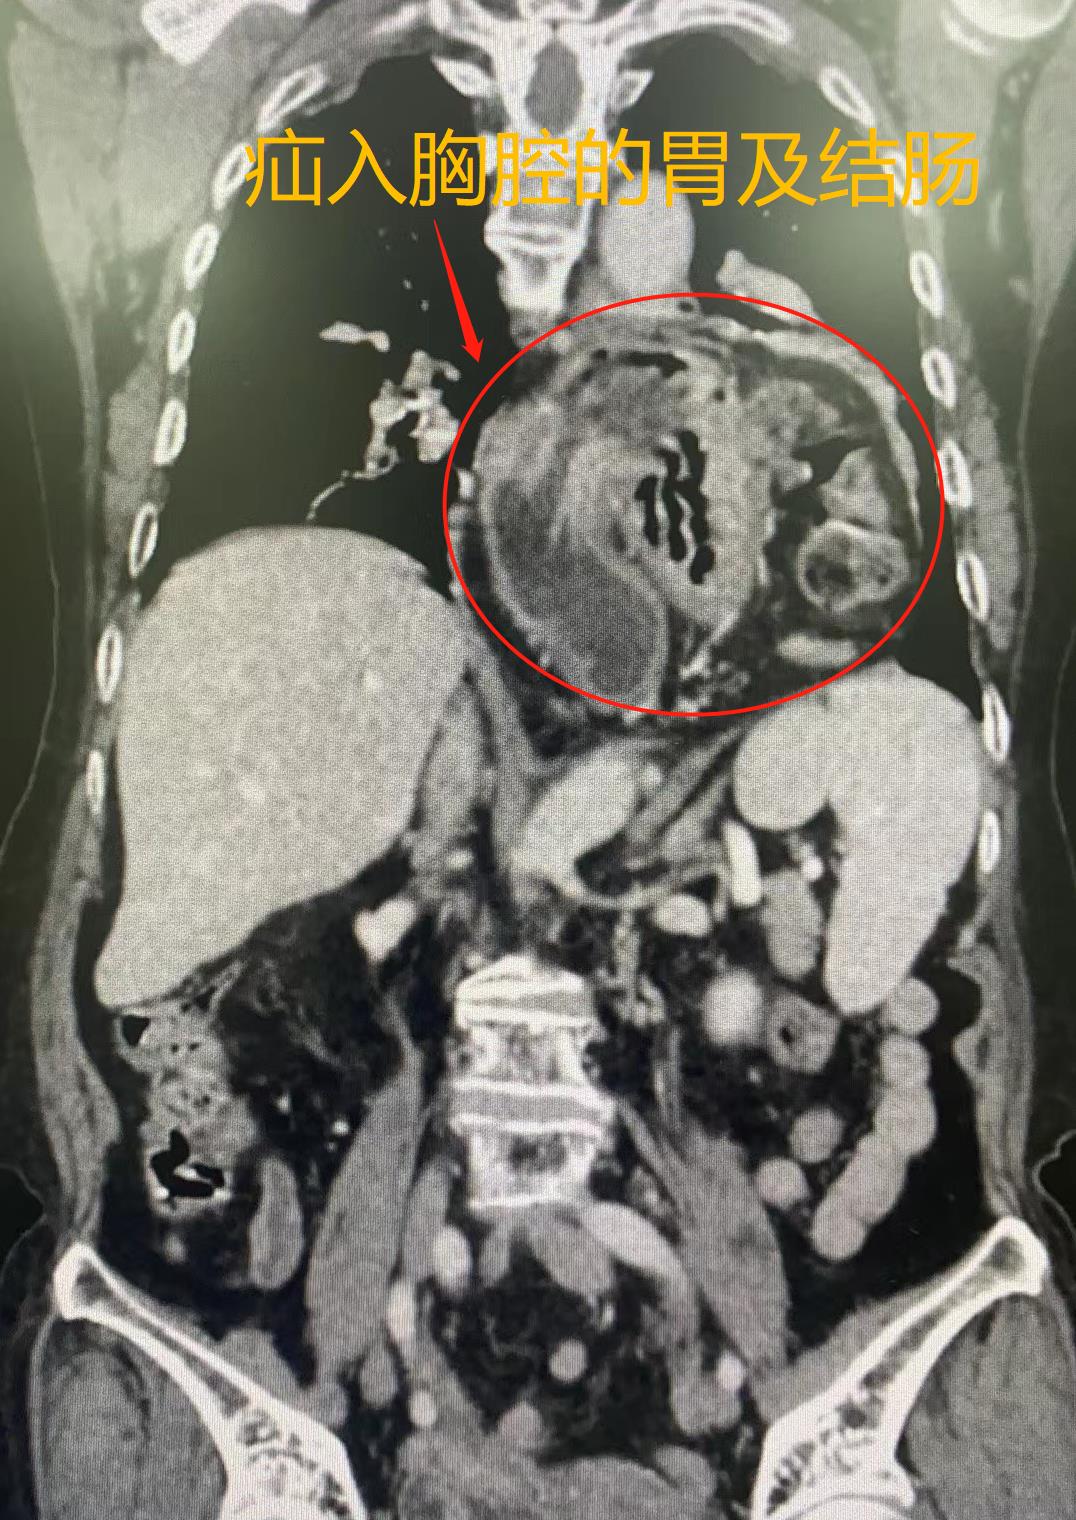

入院后,朱利勇副教授团队为患者完善术前检查,进一步明确其巨大的食管裂孔疝。检查结果显示:患者大部分胃、部分结肠都通过食管裂孔疝入胸腔,腹内脏器进入胸腔的高度几乎高于心脏的上缘,经放射科张声旺副教授计算,其疝囊体积近600ml,而患者整个腹腔体积近3000ml左右,即约五分之一腹腔脏器都进入胸腔内。同时,由于高龄及疝的影响,加之患者合并心动过缓、房性逸搏、室性早搏等诸多心律失常问题,手术操作难度大,麻醉有存在心脏骤停等风险,术后腹腔容积快速增大也有引发腹腔间隔室综合征可能。因此,术前胃肠外科Ⅱ科联合麻醉科、ICU、心内科、影像科、胸外科对患者进行多学科会诊,制备周密方案;在与患者及家属充分沟通手术风险后,于8月7日行手术治疗。

图为患者术前腹部CT显示疝入胸腔的巨大疝囊